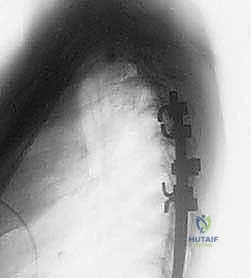

عملية دمج الفقرات (Spinal Fusion) هي إجراء جراحي يهدف إلى ربط فقرتين أو أكثر بشكل دائم، مما يزيل الحركة غير الطبيعية والمؤلمة بينهما، ويعيد الاستقرار الميكانيكي إلى العمود الفقري. في حالتنا هذه، يتم التركيز بشكل خاص على المنطقة الصدرية القطنية (Thoracolumbar Junction)، وهي المنطقة الانتقالية الحرجة التي تربط الجزء العلوي من الظهر (القفص الصدري الصلب) بالجزء السفلي (المنطقة القطنية المتحركة). يتم التثبيت باستخدام أدوات طبية معدنية متطورة (Instrumentation) مثل المسامير السويقية (Pedicle Screws) والقضبان المصنوعة من التيتانيوم.

المنطقة الصدرية القطنية (Thoracolumbar Junction): نقطة الضعف الميكانيكية

هذه المنطقة (من T11 إلى L2) تعتبر نقطة انتقال ميكانيكي حرجة. الجزء الصدري فوقها صلب ومقيد بالقفص الصدري، بينما الجزء القطني تحتها مرن ومتحرك. هذا الانتقال المفاجئ من الصلابة إلى المرونة يجعل هذه المنطقة عرضة بشكل غير متناسب للكسور الرضية (مثل كسور الانفجار بسبب حوادث السيارات أو السقوط من ارتفاع) والإجهاد الميكانيكي الذي يؤدي إلى الانزلاق الفقاري.